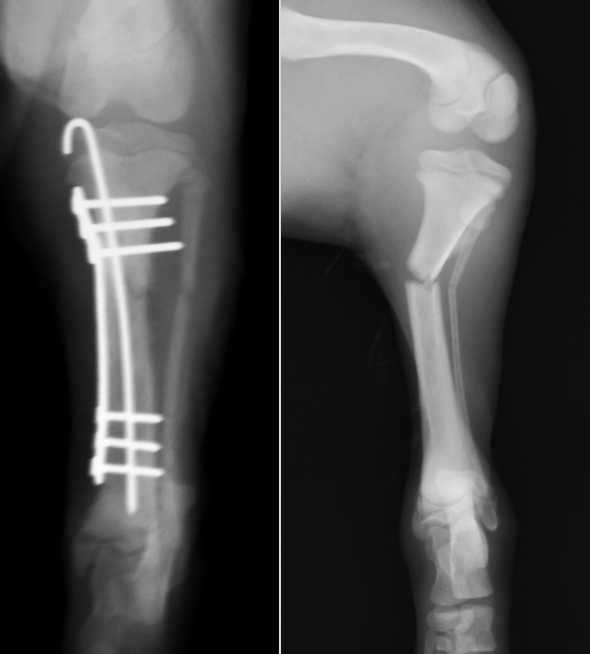

脛骨遠位のら線状骨折です。2枚のプレートで固定しています。この部位は軟部組織が少ないため、開放骨折になったり、治癒が遅れることがあるため、注意が必要です。